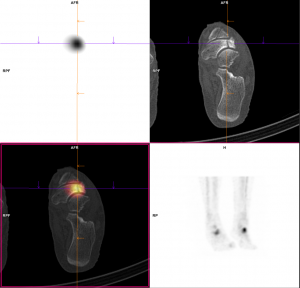

Aux temps angioscintigraphique et précoce :

Hypervascularisation avec hyperhémie tissulaire focale centrées sur les deux naviculaires, prédominant du côté gauche.

Au temps tardif et sur la SPECT-CT complémentaire :

A gauche, hyperfixation focale en regard d’une fragmentation de la partie latérale de l’os naviculaire, avec aspect condensé, et en « virgule » de l’os.

Pour mémoire, matériel de chirurgie d’hallux valgus, sans hyperfixation associée.

A droite, aspect relativement similaire avec hyperfixation focale du versant latéral du naviculaire, trame osseuse condensée et aspect en virgule.